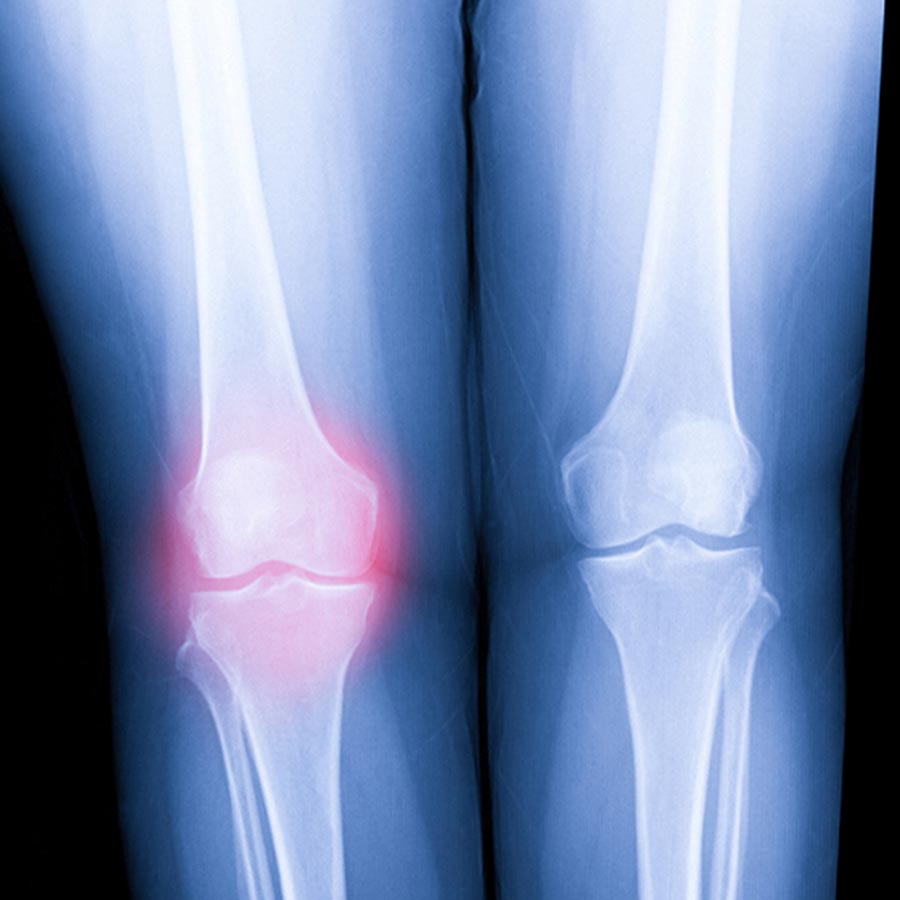

Work injuries can affect anyone – from office workers and healthcare professionals to construction crews and service industry employees. Whether it’s the result of a slip and fall, poor ergonomics, repetitive motion, or heavy lifting, these injuries often lead to lingering pain, reduced mobility, and lost productivity. Left untreated, they can turn into long-term problems that affect your health, income, and quality of life.

Workplace injuries account for over 2 million medical visits each year, and many involve the spine, joints, or nervous system. Chiropractic care is often one of the most effective, non-invasive recovery tools available.